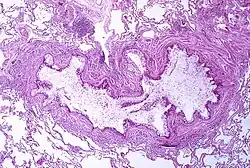

Fisiopatologia

A asma é o resultado da inflamação crónica das vias respiratórias, a qual provoca uma contração crescente dos músculos lisos envolventes. Isto provoca o estreitamento das vias e os sintomas clássicos do som sibilante ao respirar. Este estreitamento é geralmente reversível, com ou sem tratamento. Ocasionalmente, verificam-se alterações nas próprias vias respiratórias.[31] As alterações mais vulgares são o aumento de eosinófilos e o espessamento do tecido linfoide. Em casos crónicos, o músculo liso das vias respiratórias pode aumentar de tamanho, a par de um aumento do número de mucosas. No processo estão também envolvidos outros tipos de células, como os linfócitos T, macrófagos e neutrófilos, e outros componentes do sistema imunitário, como citocinas, quimiocinas, histamina e leucotrienos.[17]